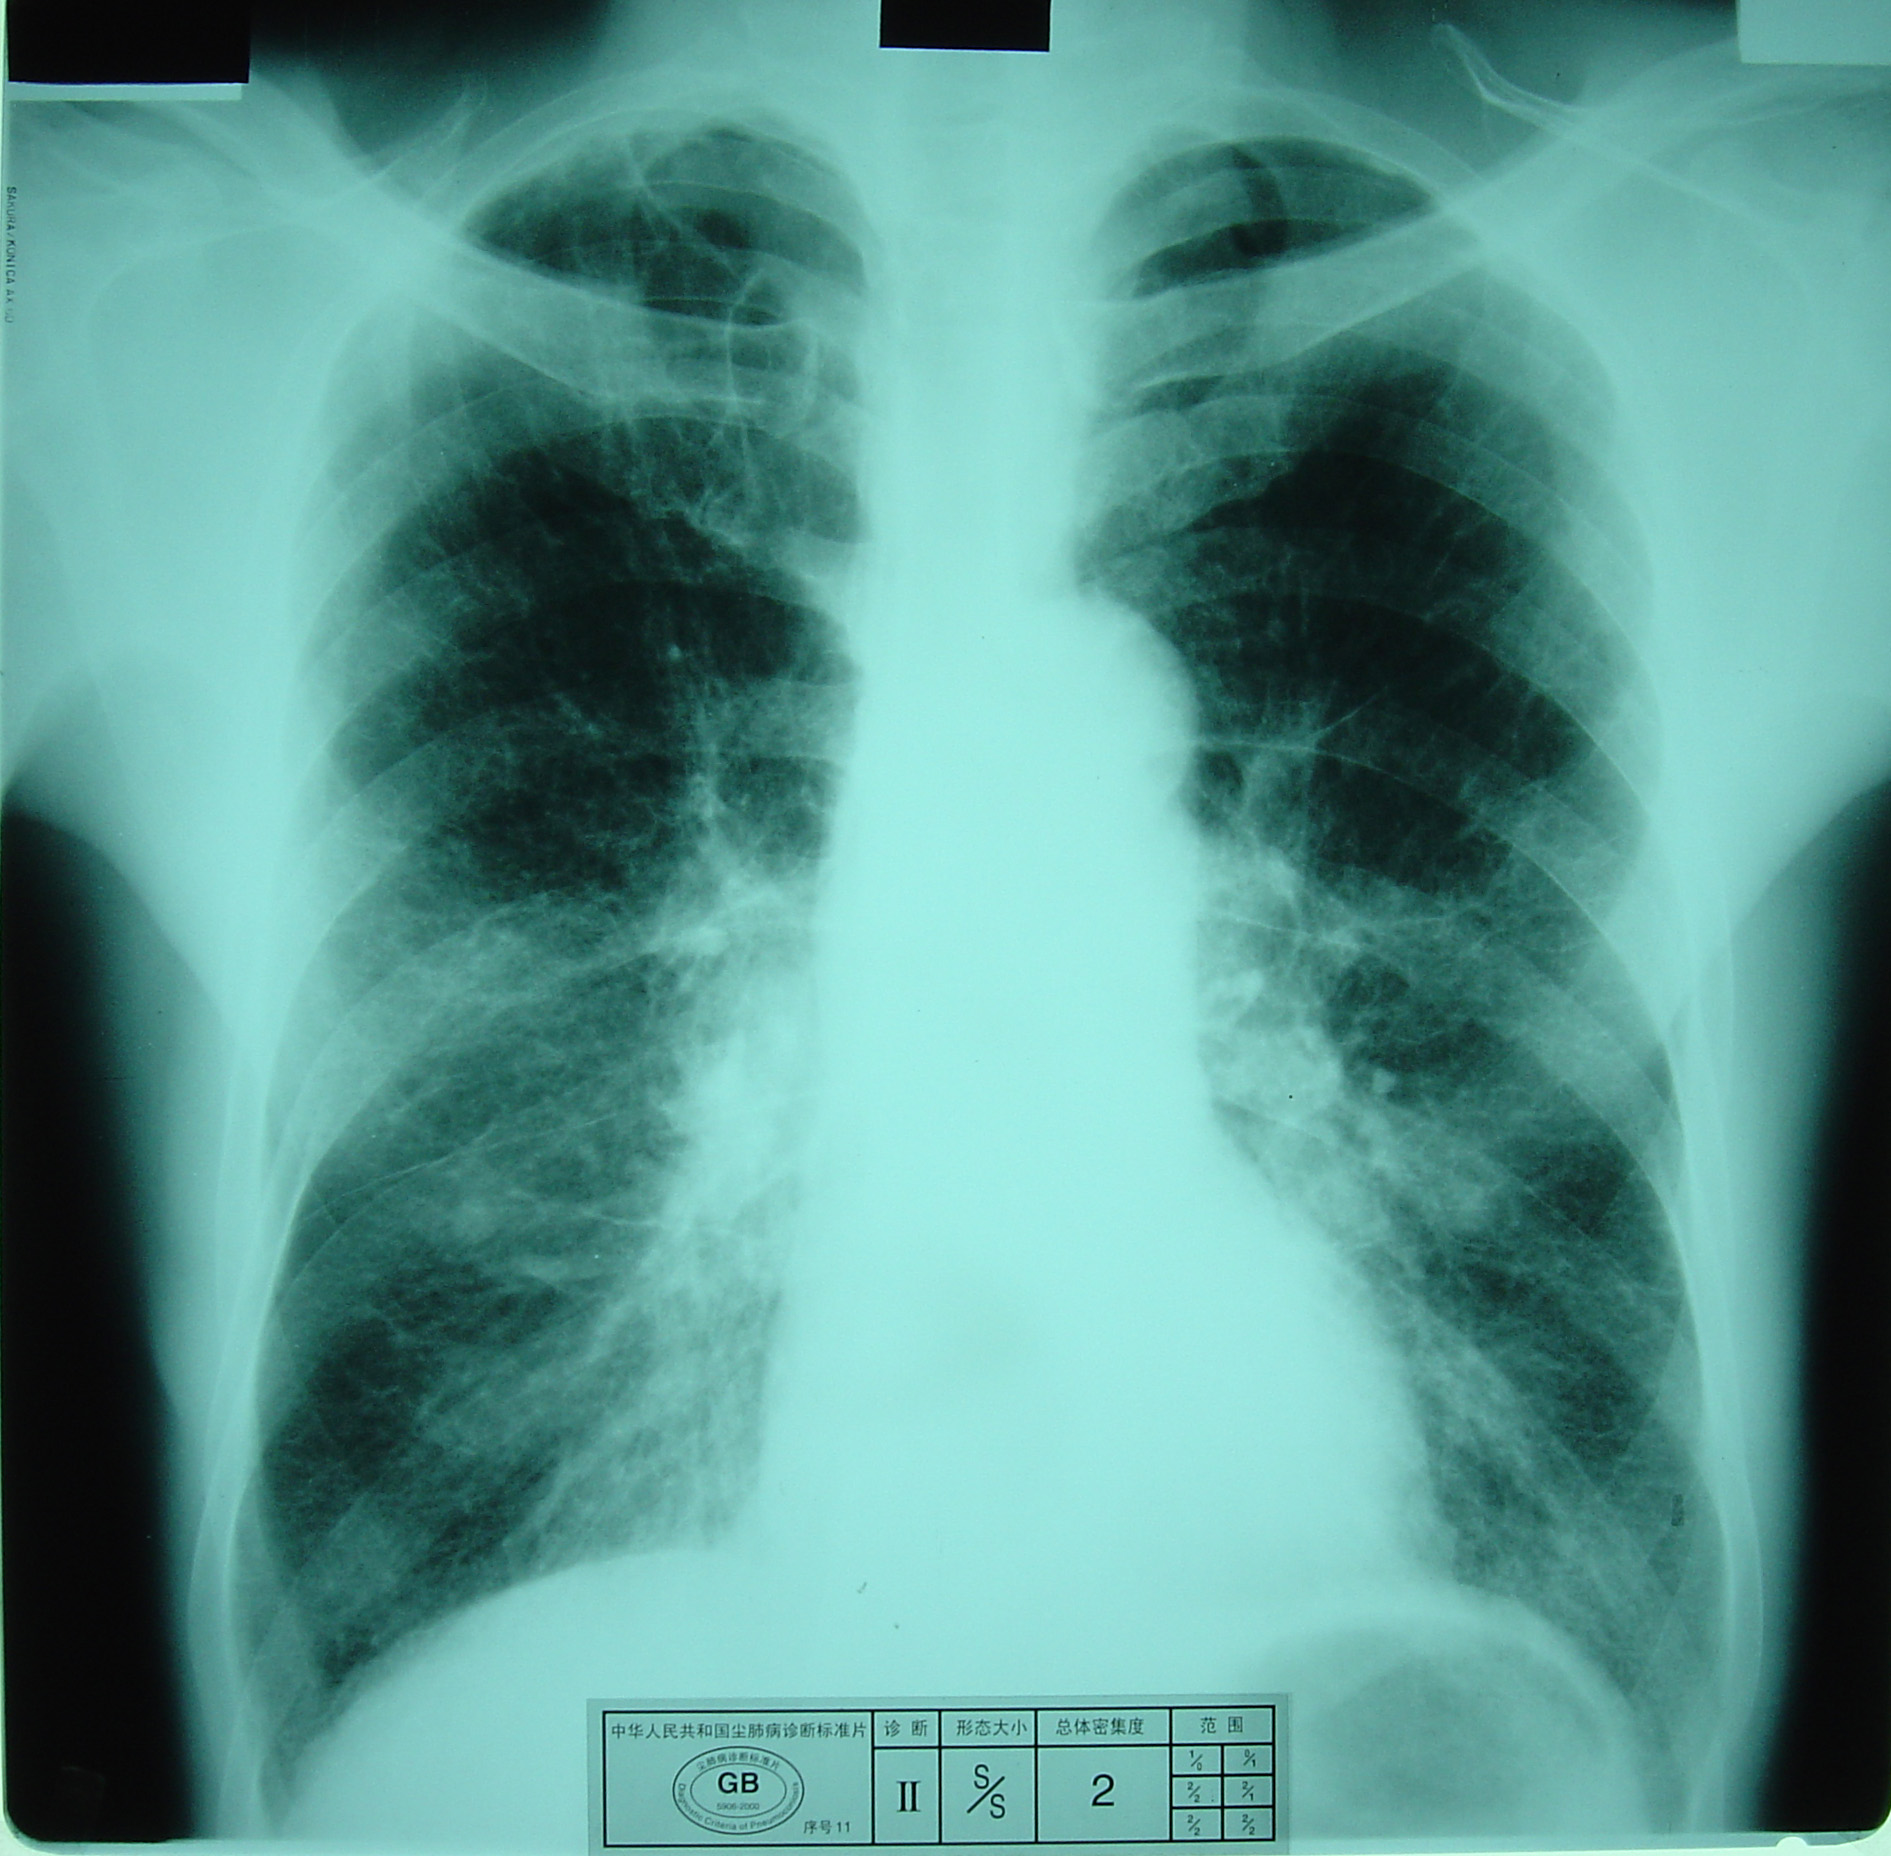

(2)X射线胸片表现:矽肺X射线胸片影像是肺组织矽肺病理形态在X射线胸片的反映,是“形”和“影”的关系,与肺内粉尘蓄积、肺组织纤维化的病变程度有一定相关关系,但由于多种原因的影响,并非完全一致。这种X射线胸片改变表现为X射线通过病变组织和正常组织对X射线吸收率的变化,呈现发“白”的圆形或不规则形小阴影,作为矽肺诊断依据。X射线胸片上其他影像,如肺门变化、肺气肿、肺纹理和胸膜变化,对矽肺诊断也有参考价值。在X射线胸片上,肺野内直径或宽度不超过10mm的阴影。小阴影按其形成分为圆形和不规则形两类。

1)圆形小阴影:是矽肺最常见和最重要的一种X线表现形态,其病理基础以结节型矽肺为主,呈圆或近似圆形,边缘整齐或不整齐,直径小于10mm,按直径大小分为p(<1.5mm)、q(1.5~3.0mm)、r(3.0~10mm)三种类型。p类小阴影主要是不太成熟的矽结节或非结节性纤维化灶的影像,q、r类小阴影主要是成熟和较成熟的矽结节,或为若干个小矽结节的影像重叠。圆形小阴影早期多分布在两肺中下区,随病变进展,数量增多,直径增大,密集度增加,波及两上肺区。

圆形小阴影(q类小阴影)

a) 有总体密集度2级的小阴影,分布范围超过4个肺区;

b)有总体密集度3级的小阴影,分布范围达到4个肺区。

尘肺贰期

尘肺贰期

尘肺贰期

尘肺贰期

尘肺贰期